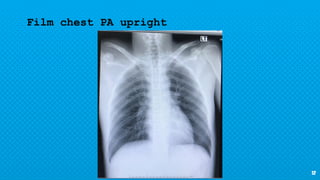

× CXR : not seen fx.

Film chest PA upright